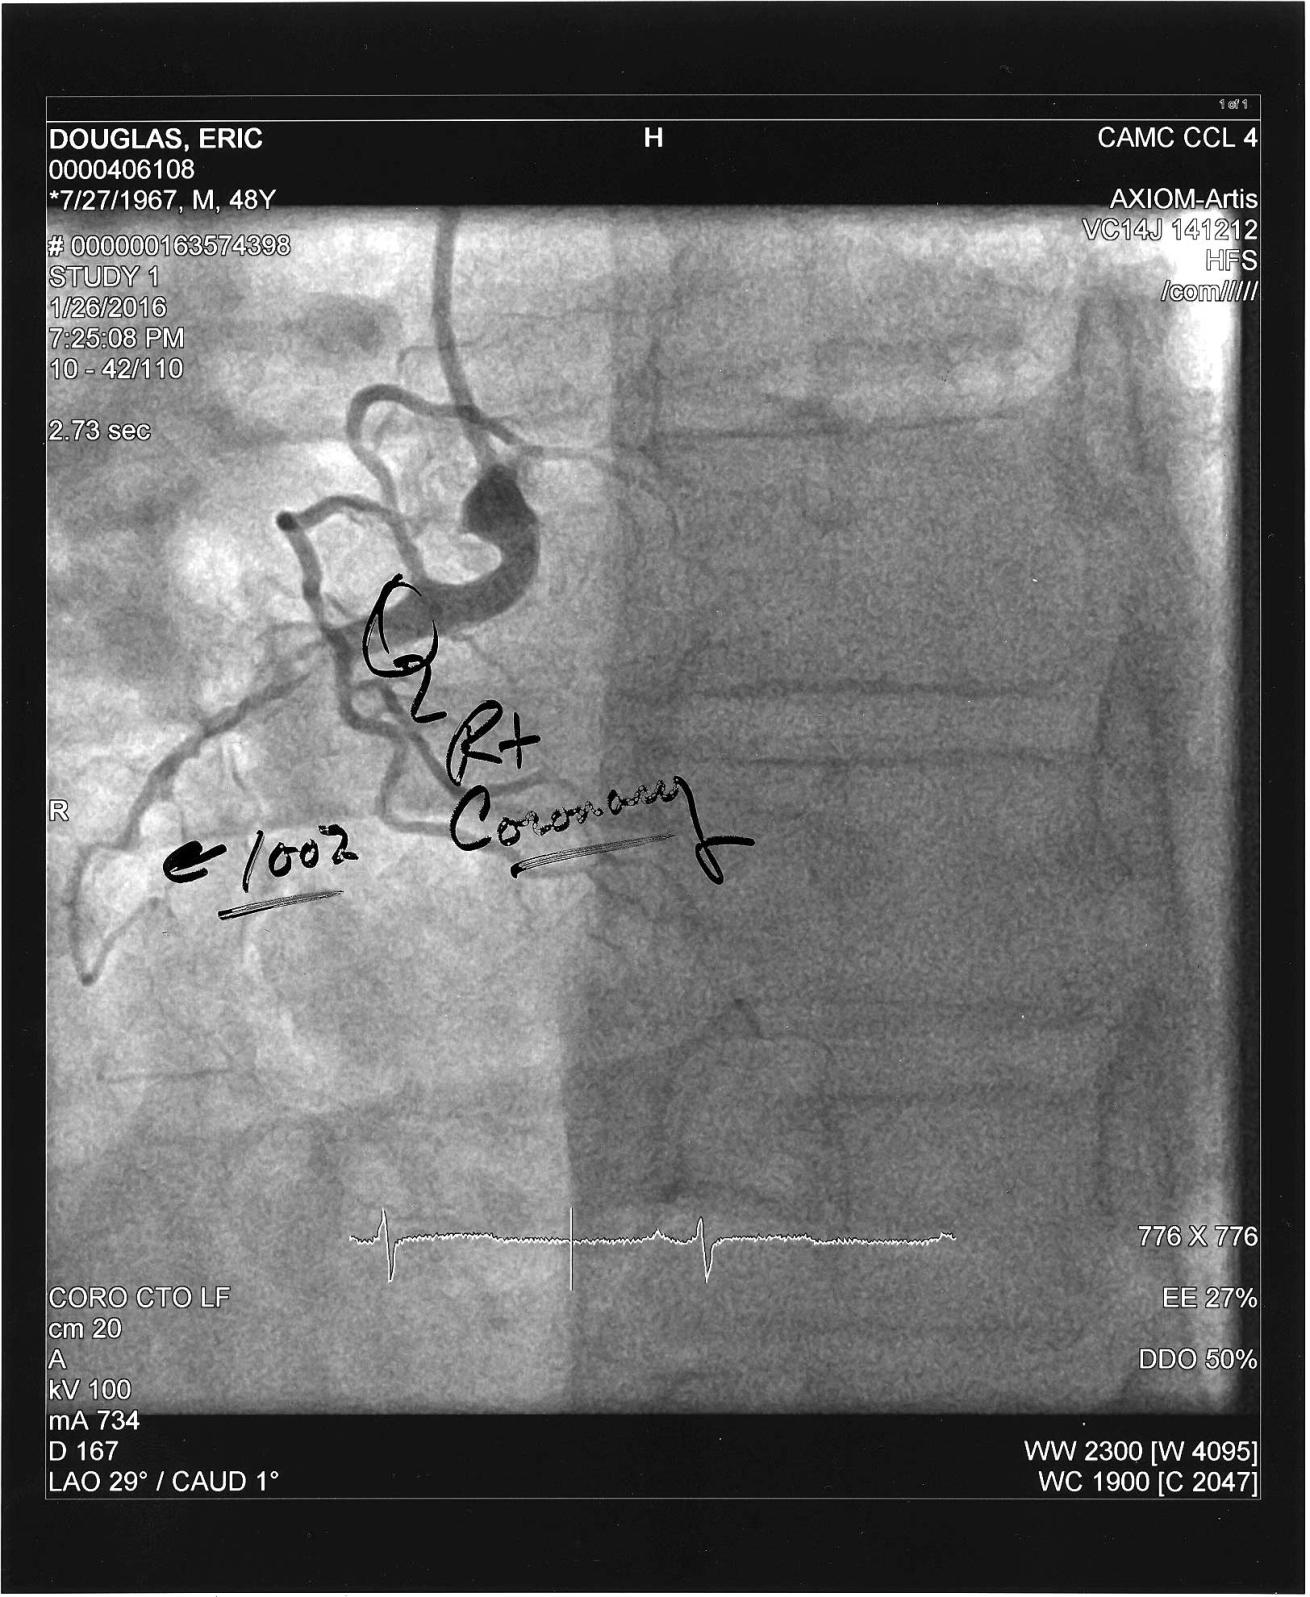

Courtesy Eric DouglasA picture of the heart catheterization that revealed blockages and restrictions in the author's coronary arteries requiring bypass grafts.

This particular explanation was interesting to me. I had a heart attack, but didn’t realize what was actually happening at the time. I wrote about that in the first Heart Disease and Diving column. It wasn’t until my cardiologist gave me a heart catheterization that I actually knew that I’d had a heart attack. As I understand it, my heart muscle showed some signs of injury, but it wasn’t severe enough that it caused any worry. They had seen worse and felt that once they restored normal blood flow to my heart muscle, it should heal and return to normal function. That was good news for me and diving: I wouldn’t have been able to get back at it if my heart wasn’t pumping at full capacity.